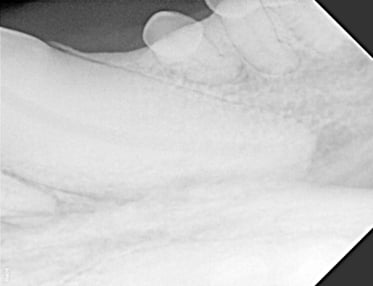

Below: Radiograph of CCF - crown, before RCT and restoration

%20Case%202%20-%20July%202024/Radiograph%20of%20ccf%20before%20rct.jpg?width=285&height=219&name=Radiograph%20of%20ccf%20before%20rct.jpg)

%20Case%202%20-%20July%202024/Apex%20radiograph%20before%20RCT.jpg?width=373&height=287&name=Apex%20radiograph%20before%20RCT.jpg)